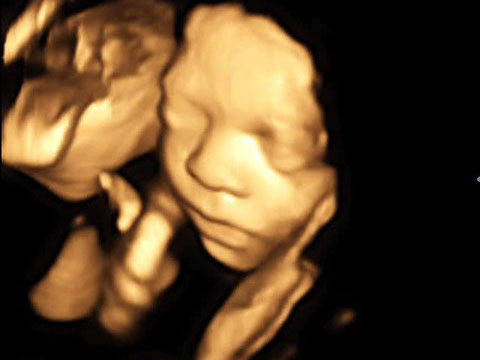

Der 4D-Ultraschall ist eine Methode der Ultraschall-Untersuchung, bei der das Ultraschallgerät ein dreidimensionales Bild des Untersuchungsobjekts in Echtzeit erzeugt.

Er dient in erster Linie der Erkennung einer Entwicklungsstörung, bzw. Fehlbildung des Kindes. 95% der Fehlbildungen bei Kindern können mittels moderner Ultraschall-Technologie heute bereits vor der Geburt erkannt werden.

Die 4D-Ultraschallsonographie hilft durch eine optimale Betreuung in der Schwangerschaft Schäden in Grenzen zu halten, bei bestimmten Problemen ist es sogar noch möglich, während der Schwangerschaft einzugreifen.